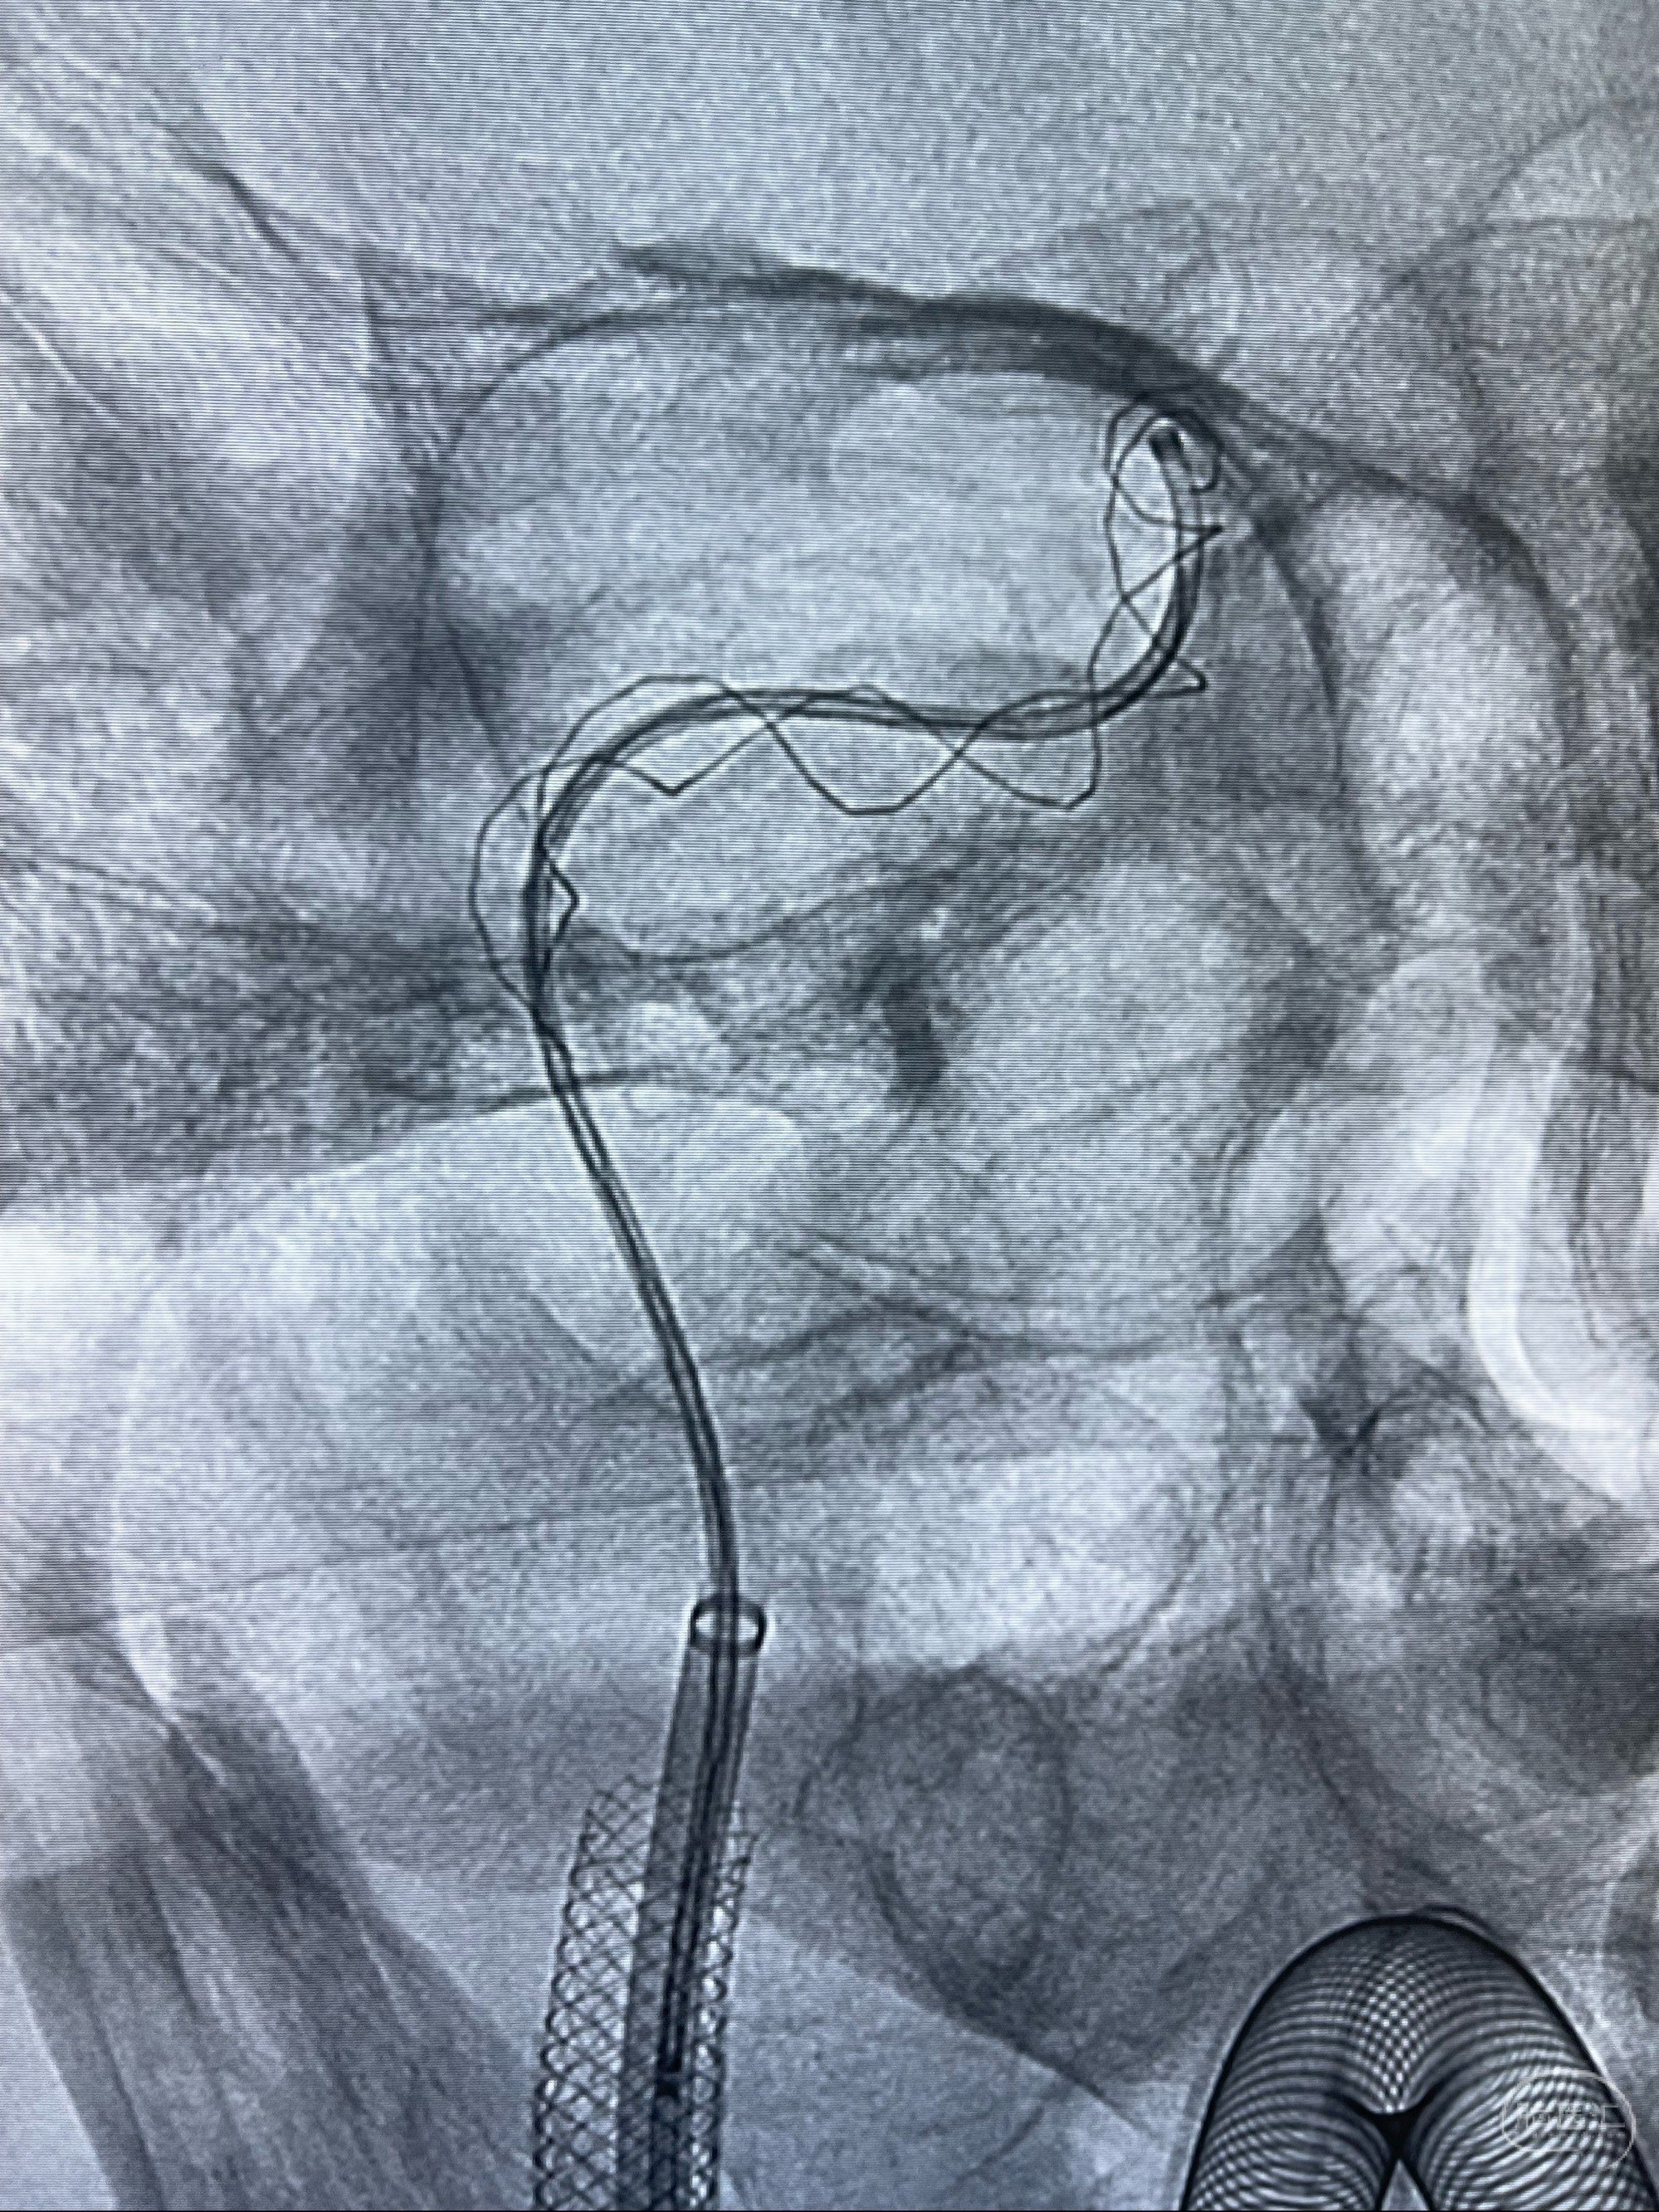

双抗准备后于2023-07-13在全麻下行右侧颈内动脉功能保护

088NeuroMAX100cm长鞘在125cmMPA及黑泥鳅导丝引导下超选择性插入右侧颈内动脉支架内

经导引导管造影显示支架远端颈内动脉不规则狭窄伴局部充盈缺损,同时行全身肝素化5ml

支架完全打开,近心端位于原颈动脉支架远心端内